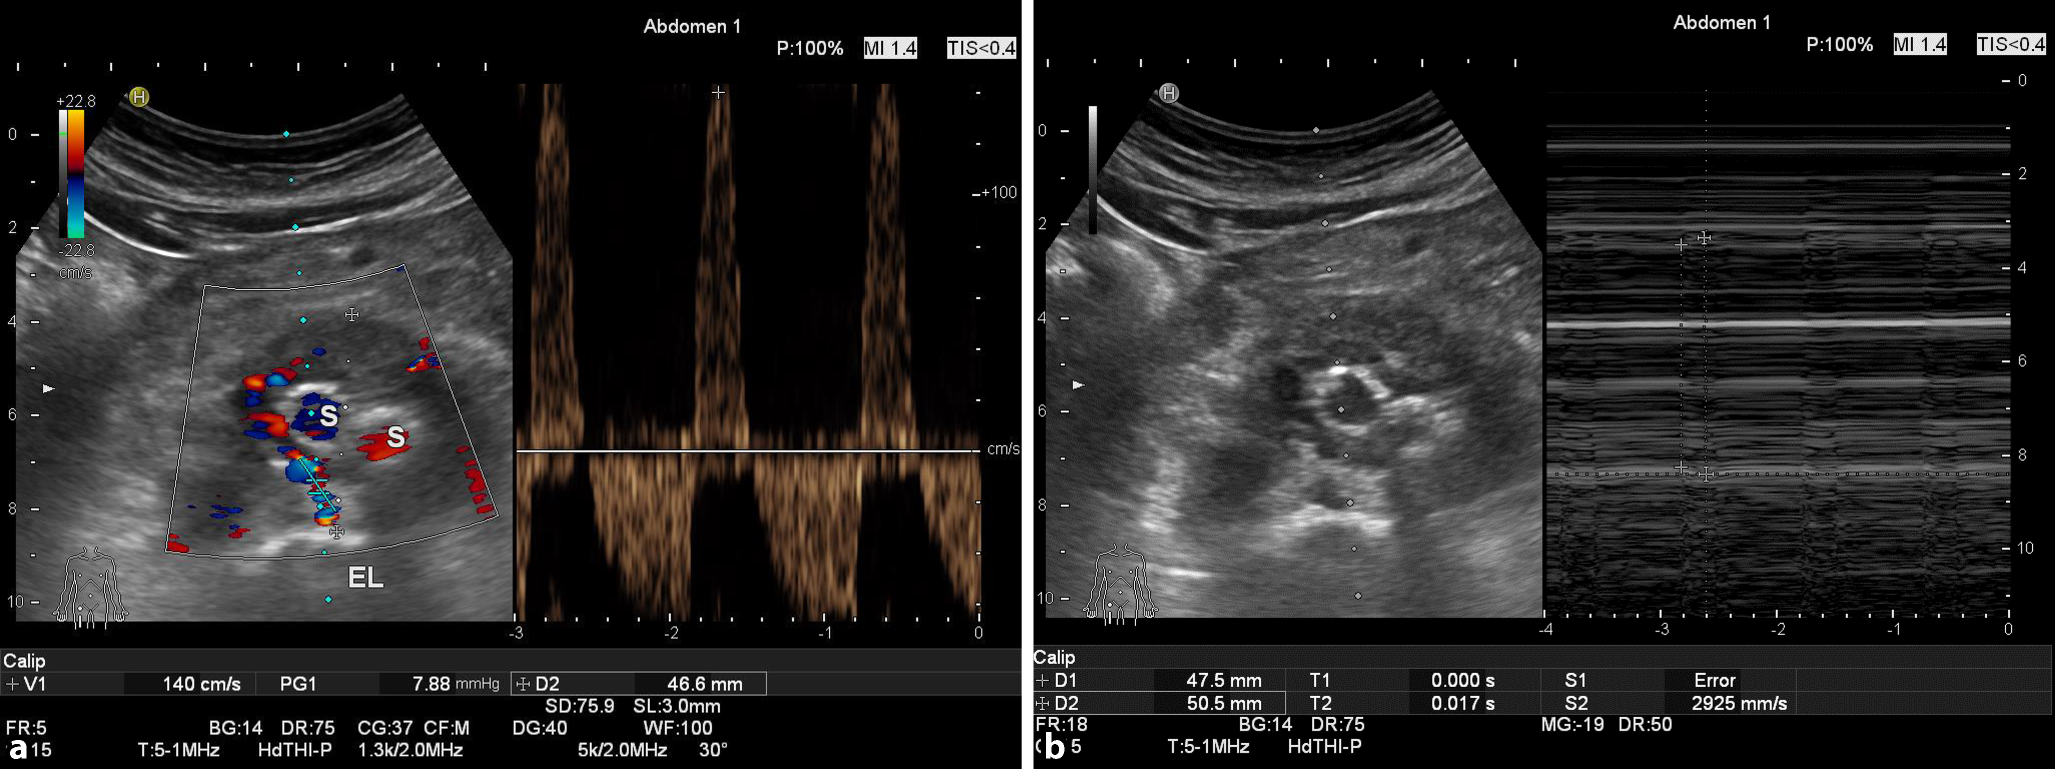

Neben Versuchen, die Therapierelavanz durch die systolische Spitzengeschwindigkeit („peak systolic velocity“, PSV) ostiumnah in High-flow- und Low-flow-Endoleaks (Abb. 8a) zu quantifizieren [81], kann auch die im Time-motion-Modus nachgewiesene Pulsation im Restsack als Ausdruck des Druckaufbaus im Restsack durch ein therapiebedürftiges Endoleak gewertet werden (Abb. 8b).

Abb. 8

a High-flow-Endoleak, farbduplexsonographisch dargestellt mit einer systolischen Spitzengeschwindigkeit („peak systolic velocity“, PSV) von >140 cm/s im Dopplerfrequenzspektrum (S Stentbeinchen) mit typischer Pendelströmung aus einer Lumbalarterie. b Die systolisch-diastolische Pulsation von >3 mm im Aneurysmarestsack drückt den Druckaufbau durch ein therapiebedürftiges Endoleak in einem durch EVAR („endovascular aortic repair“) ausgeschalteten AAA aus (Darstellung wie in a, nur etwas weiter kranial)